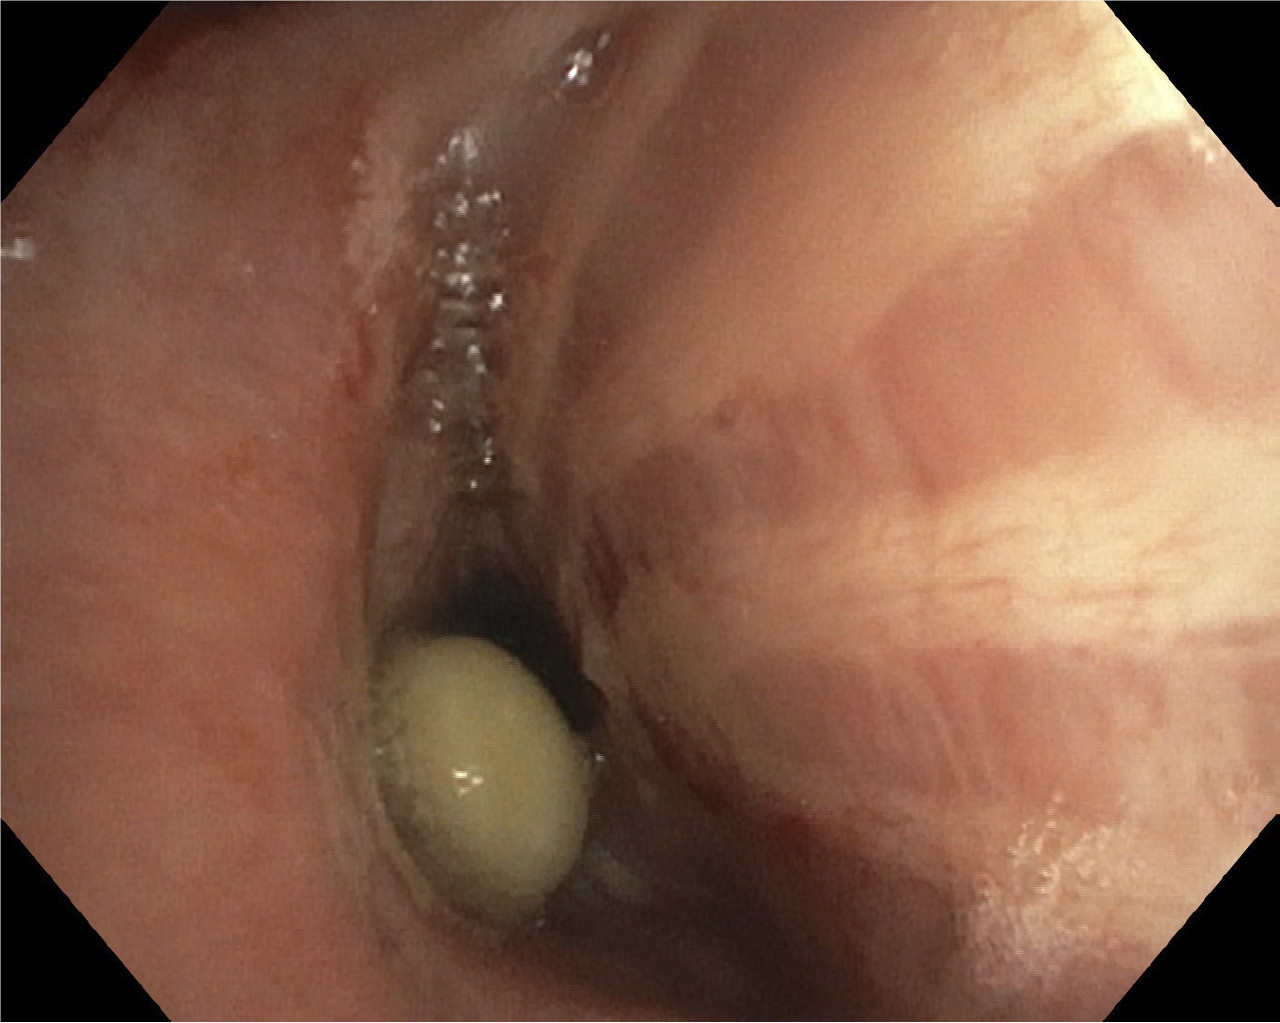

A bronchoscopy was performed (see endoscopy image) and a pea was located as described at the CT examination and subsequently removed (see video). The pea was intact with a diameter of approximately 10 mm. The patient was fever- and symptom-free in a little less than a week, and a chest x-ray eight weeks later showed complete remission of the atelectasis. A further bronchoscopy also revealed normal findings.